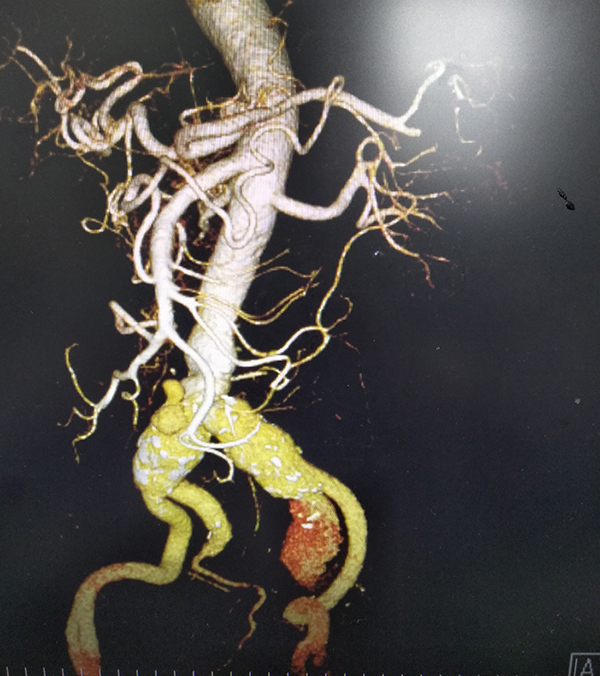

近日,我院胸心血管外科、放射科、介入导管室等多科室合作,成功地为一位患有腹主动脉夹层动脉瘤+双侧髂总动脉瘤+左侧髂内动脉瘤破裂的危重患者施行动脉瘤腔内覆膜支架植入修复术,解除了人体“炸弹”的威胁,及时挽救了患者生命。

72岁的何先生,因下腹部疼痛3天急诊入院,经腹部CTA检查,被诊断为腹主动脉夹层动脉瘤、双侧髂总动脉瘤先兆破裂、左侧髂内动脉瘤破裂,病情极其危重,随时都可能有生命危险。

CT检查 10月23日,在华西医院黄斌副教授的现场指导下,胸心血管外科、放射科科、介入导管室等多科室医护人员的通力配合下,在局麻下完成经双侧股动脉腹主动脉瘤、双侧髂总动脉瘤、左侧髂内动脉瘤腔内覆膜支架修复术+左侧髂内动脉瘤、右侧髂内动脉弹簧圈栓塞术+球囊扩张术,手术过程顺利,患者获得成功救治。术后当日患者恢复饮食,第二天下床活动,1周后康复出院。

腹主动脉瘤腔内覆膜支架修复术后 腹主动脉瘤腔内覆膜支架修复术(EVAR)是目前治疗腹主动脉瘤的一种微创外科技术,其手术创伤较小,术后并发症少,使许多不能耐受手术的高危病人获得救治机会。但是EVAR治疗方案十分依赖腹主动脉的解剖学形态,血管腔内操作难度大,技术要求高。这次手术取得圆满成功,标志着我院胸心血管外科在腹主动脉瘤的诊治水平又上了新台阶。(文:韦连素)